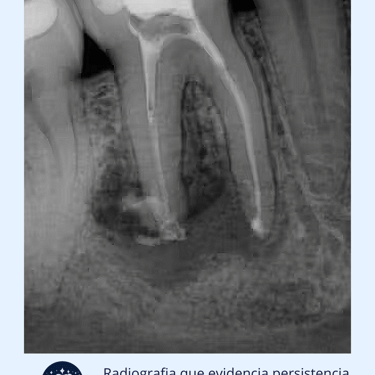

Radiografías: Se toman radiografías para evaluar el estado de los conductos radiculares tratados previamente y el hueso circundante. Las radiografías ayudan a detectar cualquier signo de reabsorción ósea, abscesos o fracturas radiculares.